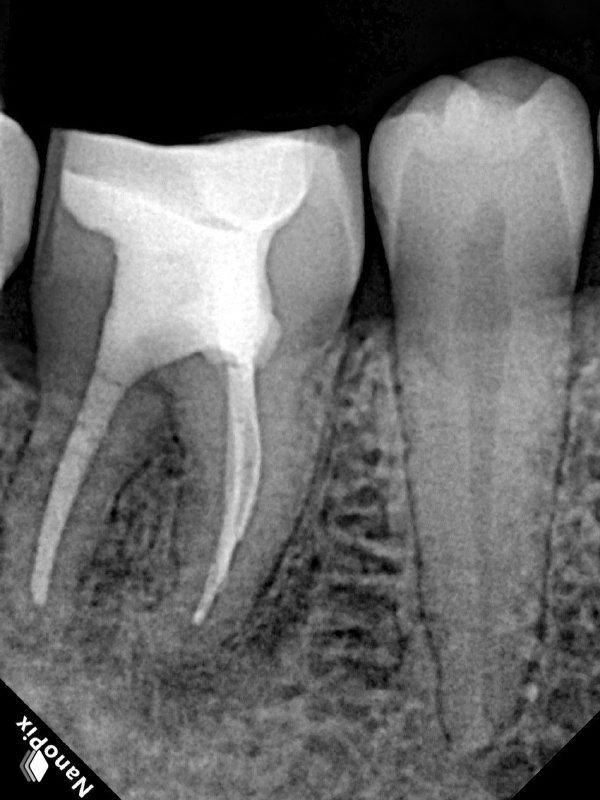

- 6)Оставляю кальций на неделю для профилактики заместительной резорбции. Она все равно будет на реколлах, но в меньшем объеме.

- 7) Пломбирую вертикальной компакцией гуттаперчи, в то же посещение делаю билдап. А вот коронкой зуб покрывает уже через 6 мес после реколла.